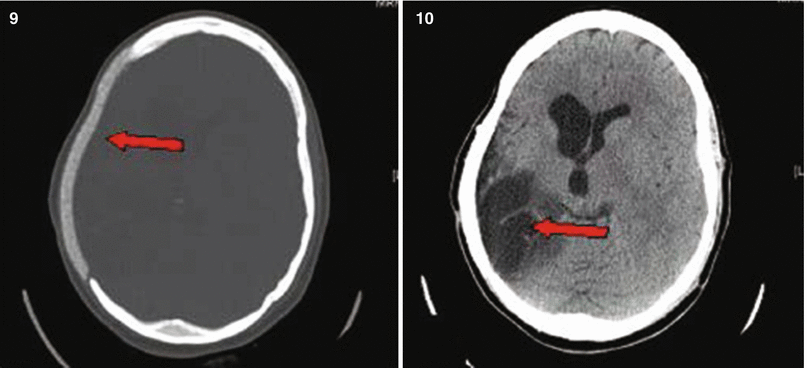

Fig. 27.4

Patient No. 4: a 26-year-old male, who sustained a solitary GSW to the head from distant range. Entry wound at the R ear canal, no exit wound. Plates 1 and 2: scout images A/P and lateral with evidence of multiple bullet fragments on the R extracranially and bilaterally intracranially. Note the large R-sided skull fracture. Arrows in panel 3 an 4 point at the bullet tract as seen on head CT with axial bone windows (3) and in matching coronal reconstructions (4). There are interspersed metal bullet fragments visible with their streak artifact. Arrow in plate 5 points at the temporal lobe hematoma. Arrow in plates 6 and 7 points at the hemicraniectomy site. Arrow in plate 8 points at the R MCA bifurcation with multpiple retained bullet fragments and a surgical clip for the traumatic avulsion site. Arrow in plate 9 indicates the allograft cranioplasty. And plate 10 shows a small left frontal inraparenchymal hematoma